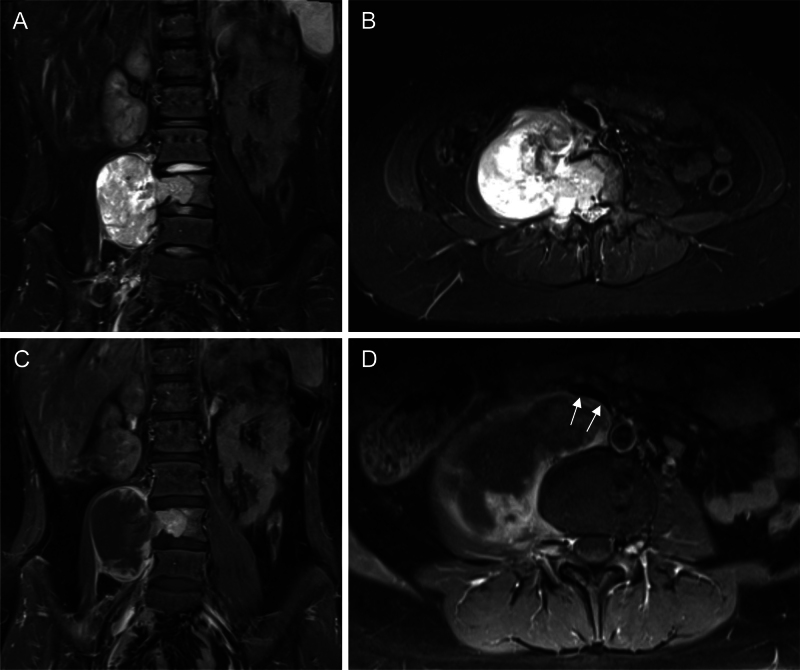

Observations: The authors present the first documented case of planned division and mobilization of the vena cava supported by venous-venous bypass in order to achieve gross-total resection of a lower lumbar malignant peripheral nerve sheathe tumor as part of a two-stage procedure.

Lessons: Inferior vena cava division and reanastomosis is a novel technique that can be used to widen surgical corridors in anterior approaches to the lumbar spine, and one that proves useful in en bloc resections. Venous-venous bypass can minimize impact on right heart filling during prolonged surgery. https://thejns.org/doi/10.3171/CASE25151.